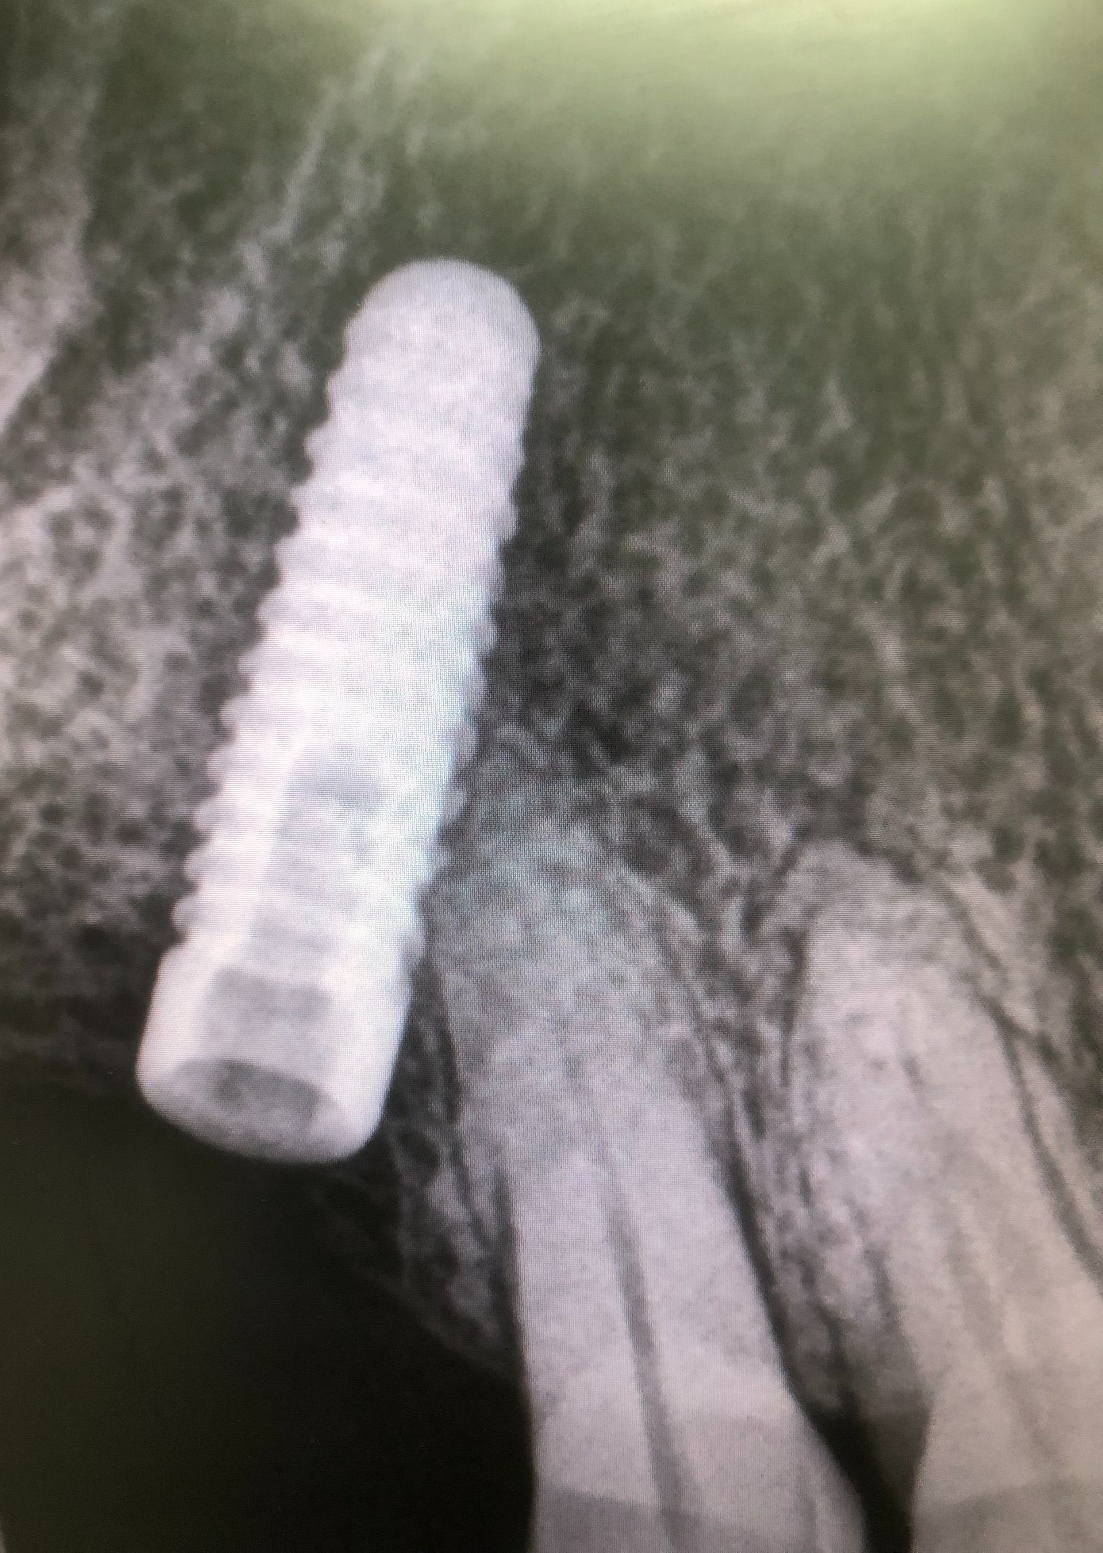

Como hemos comentado es un molar, es decir, una pieza dental en la zona posterior de la boca y con una posición del implante muy inclinada para poder esquivar el seno maxilar, lo cual dificulta mucho el trabajo.

Debido a que la rosca no salió con la vibración optamos por rehacerla. Primero, procedemos al vaciado del implante con las fresas cañón estándar. Y continuación, realizamos el paso sucesivo de los machos de roscar por dentro del vaciado conseguido. Finalmente hemos rehecho la rosca.